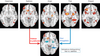

Que permet l'IRM Fonctionnel

À voir les patrons d'activation des émotions

Explique le modèle des émotions d'Hamann

La distinction qualitative des émotions est une construction de l’esprit Le cerveau utilise des structures/réseaux communs pour des émotions différentes Les émotions peuvent être représentées selon leur « Valence » et « Intensité» abscisse : Émotion les plus limité vs les plus excessives Ordonné : Gradient négativité vs positivité